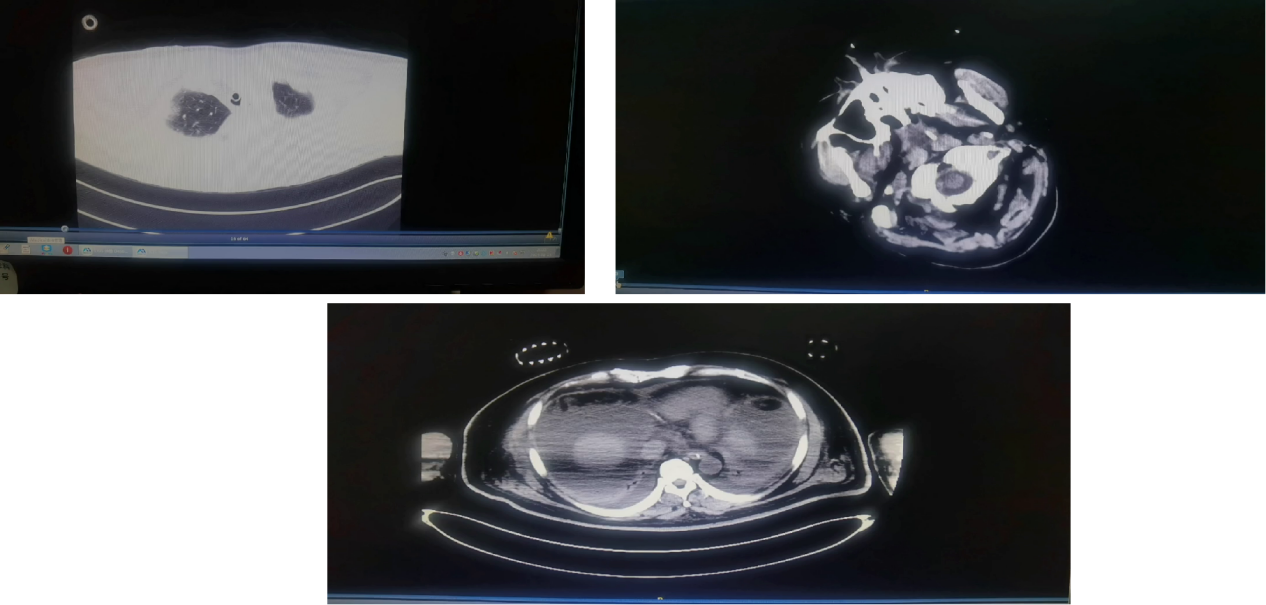

图4 影像学检查结果(5月21日)

图8 影像学检查结果(5月26日)

多学科协作,构建耐药菌感染的立体化防控网络:重症医学科通过PICCO2 监测,结合超声评估下腔静脉变异度,实施目标导向液体治疗,既保障脏器灌注,又避免容量过负荷加重肝损伤;临床药学则依术后药代特点,将头孢他啶-阿维巴坦调整为3小时持续泵入以提升抗菌效果;影像科用CT定位腹腔积液辅助引流;微生物科4小时内出具耐药基因检测结果,形成“诊断-干预” 闭环;肝移植科平衡排斥反应与感染风险,为救治保驾护航。